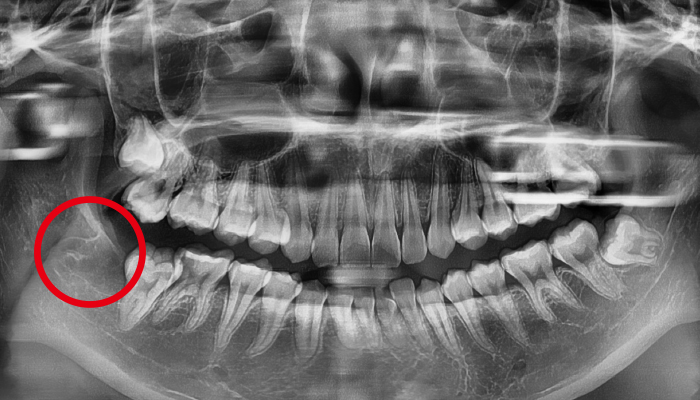

대학병원에서 해야 한다는 어려운 케이스의 사랑니도 발치합니다.

사랑니가 신경과 맞닿아 있는 상황을 제외하고는 안전하고 신속하게 발치가 가능합니다. 사랑니가 비스듬하게 누워있는 경우에는 수술적인 방법을 통해 발치를 해야합니다.

신경과 맞닿아 있는 경우에는 신경손상의 우려가 있음으로 주의하셔야 합니다. 때문에 사랑니 발치는 많은 경험을 가진 의료진에게 받아야 합니다.

사람에 따라 다르지만 사랑니는 대부분 뼈의 자리가 부족하거나 기울어져 나거나 일부분에만 나오게 되어 관리가 매우 힘들고 인접 치아에 충치까지 유발할 수 있습니다. 매복사랑니는 고난이도 기술이기 떄문에 숙련된 의사의 발치가 중요합니다.

사랑니 발치 전후 사례